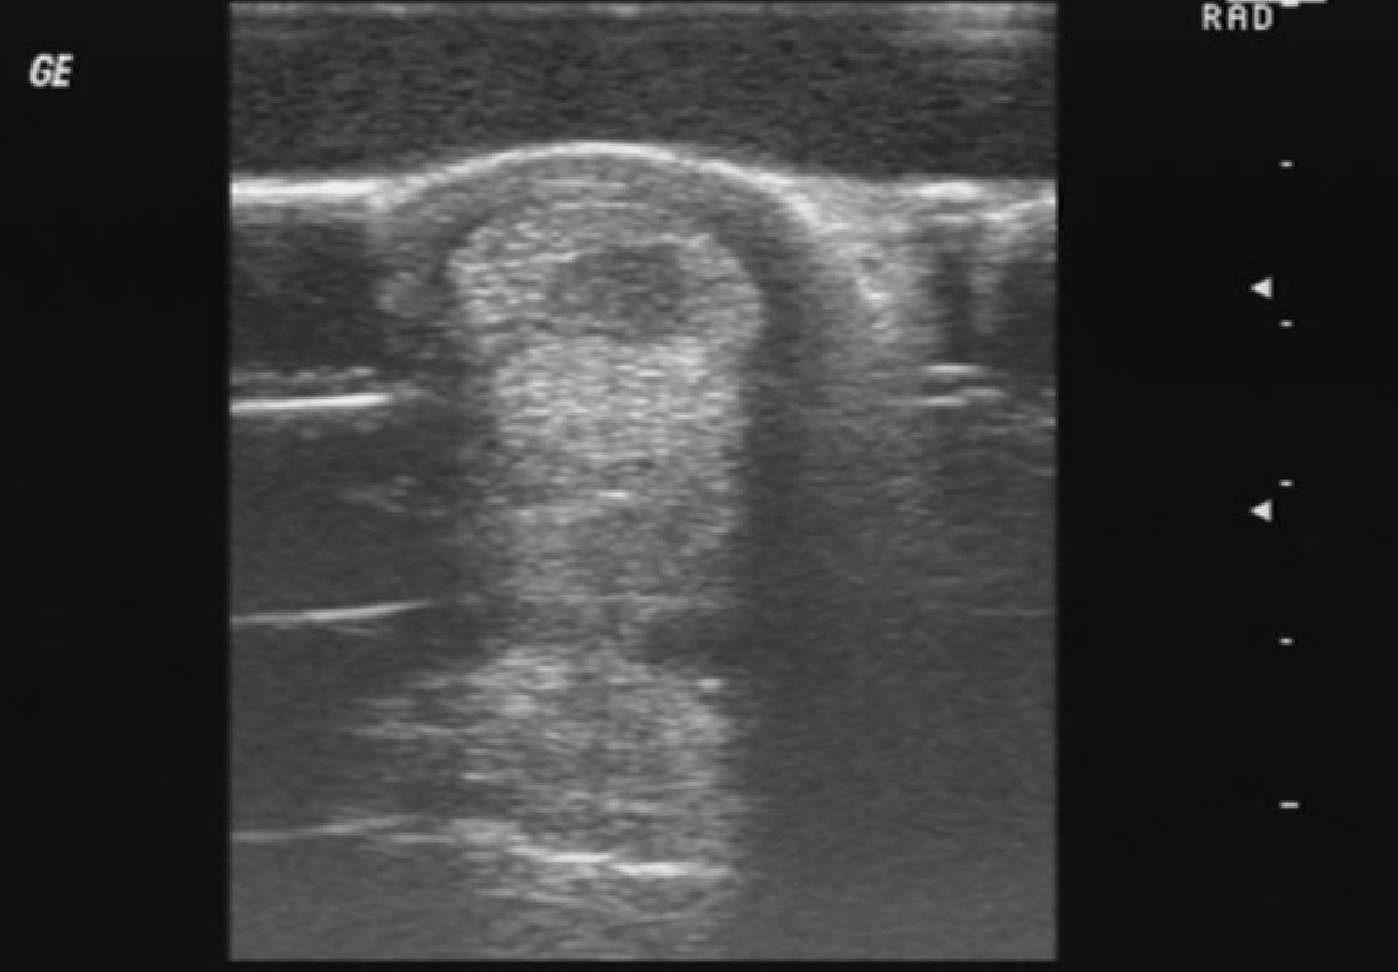

Der Ultraschall, medizinisch als Sonografie bezeichnet, gehört aufgrund seiner einfachen und nicht invasiven Durchführung neben dem Röntgen zum Standard in der Tiermedizin. Mit ihm können verschiedene innere Bereiche des Körpers zweidimensional sichtbar gemacht werden.

Unter Ultraschall versteht man Schallwellen, die oberhalb des Hörfrequenzbereichs des Menschen liegen. Im Ultraschallgerät werden elektrische Kristalle durch eine Wechselspannung zum Schwingen gebracht. Die dadurch entstehenden Ultraschallwellen werden über den Schallkopf des Ultraschallgeräts an das Gewebe übertragen. Je nach Dichte der unterschiedlichen Körpergewebe werden die Schallwellen entweder reflektiert, absorbiert, gestreut oder hindurchgelassen. Die wieder im Ultraschallgerät eintreffenden Schallwellen werden in digitale Signale umgewandelt und als Bild dargestellt. Dabei stellen sich Gewebe, die einen Großteil der Schallwellen absorbieren (beispielsweise Knochen), schwarz und Gewebe, die die Schallwellen reflektieren (beispielsweise Flüssigkeiten), weiß dar. Muskulatur, Bindegewebe, Sehnen und andere Weichteile erscheinen im Ultraschallbild in unterschiedlichen Grautönen.

Die Ultraschalluntersuchung findet in der Tiermedizin ein breit gefächertes Anwendungsgebiet, da viele Gewebe bis zu einer bestimmten Eindringtiefe der Schallwellen gut dargestellt werden können. Die Durchführung ist zudem nicht schmerzhaft und in den meisten Fällen ohne Narkose durchführbar.

Zu den am häufigsten durchgeführten Ultraschalluntersuchungen gehören die Untersuchung der Bauchorgane, gynäkologische Untersuchungen sowie der Herzultraschall mit Messung der Blutstromgeschwindigkeit (siehe Artikel Echokardiographie). Beim Pferd werden außerdem häufig Sehnen, Bänder und Gelenke und auch das Becken, der Hals und der Rücken per Ultraschall untersucht.

Weiterhin kann die Ultraschalluntersuchung dabei helfen, gezielte Punktionen (=Gewebeproben) aus potenziell veränderten Organen oder Strukturen zu entnehmen. Auch Injektionen werden zum Teil unter Ultraschallkontrolle verabreicht.

Kleintiere werden für die Ultraschalluntersuchung in Rücken- oder Seitenlage auf den Untersuchungstisch gelegt. Eine Narkose ist in den meisten Fällen nicht erforderlich. Um ein bestmögliches Bild zu erhalten, wird die zu untersuchende Region geschoren und mit Alkohol entfettet. Für einen besseren Kontakt des Schallkopfes zur Haut wird Ultraschallgel benutzt.